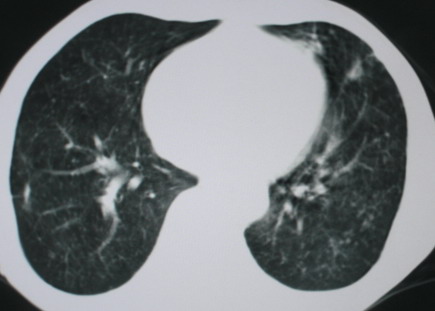

以下是引用医影拾贝在2008-6-3 18:48:00的发言:[br]双上肺弥漫性小结节影,纵隔窗内钙化淋巴结影,考虑血播性tb可能性较大,不除外肺ca可能

以下是引用卜一在2008-6-3 19:33:00的发言:[br]双肺结节,以双上肺分布为多,期间搀杂片状致密影及索条致密影。考虑:继发性肺结核伴血型播散可能性大。不除外肺泡ca的可能!另:椎体退变!

以下是引用panyishengct在2008-6-3 21:09:00的发言:[br]双上肺弥漫性小结节影,纵隔窗内钙化淋巴结影,考虑矽肺或/和tb可能性较大,不除外肺ca可能。腰椎考虑退变。 [br][br]